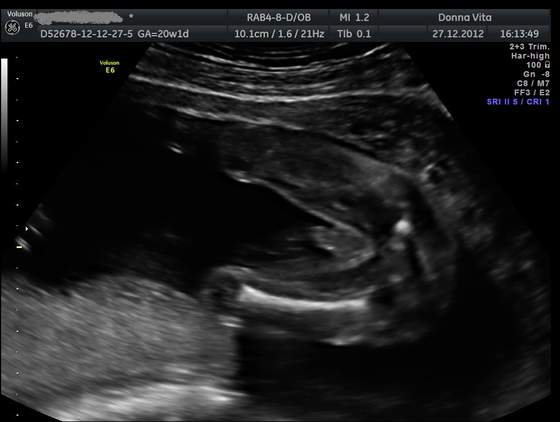

Po świętach w Lublinie u rodziców stwierdziliśmy, że pójdziemy sobie na USG 3D/4D bo tam jest więcej wyspecjalizowanych gabinetów niż w mieście w którym mieszkamy. Gin pomierzył wszystko dokładnie i serduszko ok, główka, mózg, kręgosłup i inne ważne rzeczy również. Dzidzia jest o 5 dni młodsza niż według OM, ale Gin pytał się mnie ilu dniowe miałam cykle i że wszystko jest w porządku. W trakcie pyta się czy chcemy znać płeć, a my, że oczywiście, więc mówi : JEST FUJARKA I SĄ JAJKA

Czyli moje przeczucia co do płci się sprawdziły. Mamy piękne zdjęcie synka od dołu, który pokazał się w całej swojej okazałości:-)

Dostaliśmy wydruk kilku zdjęć oraz chyba 4-5 filmików, jest taki piękny, już jestem zakochana po uszy!